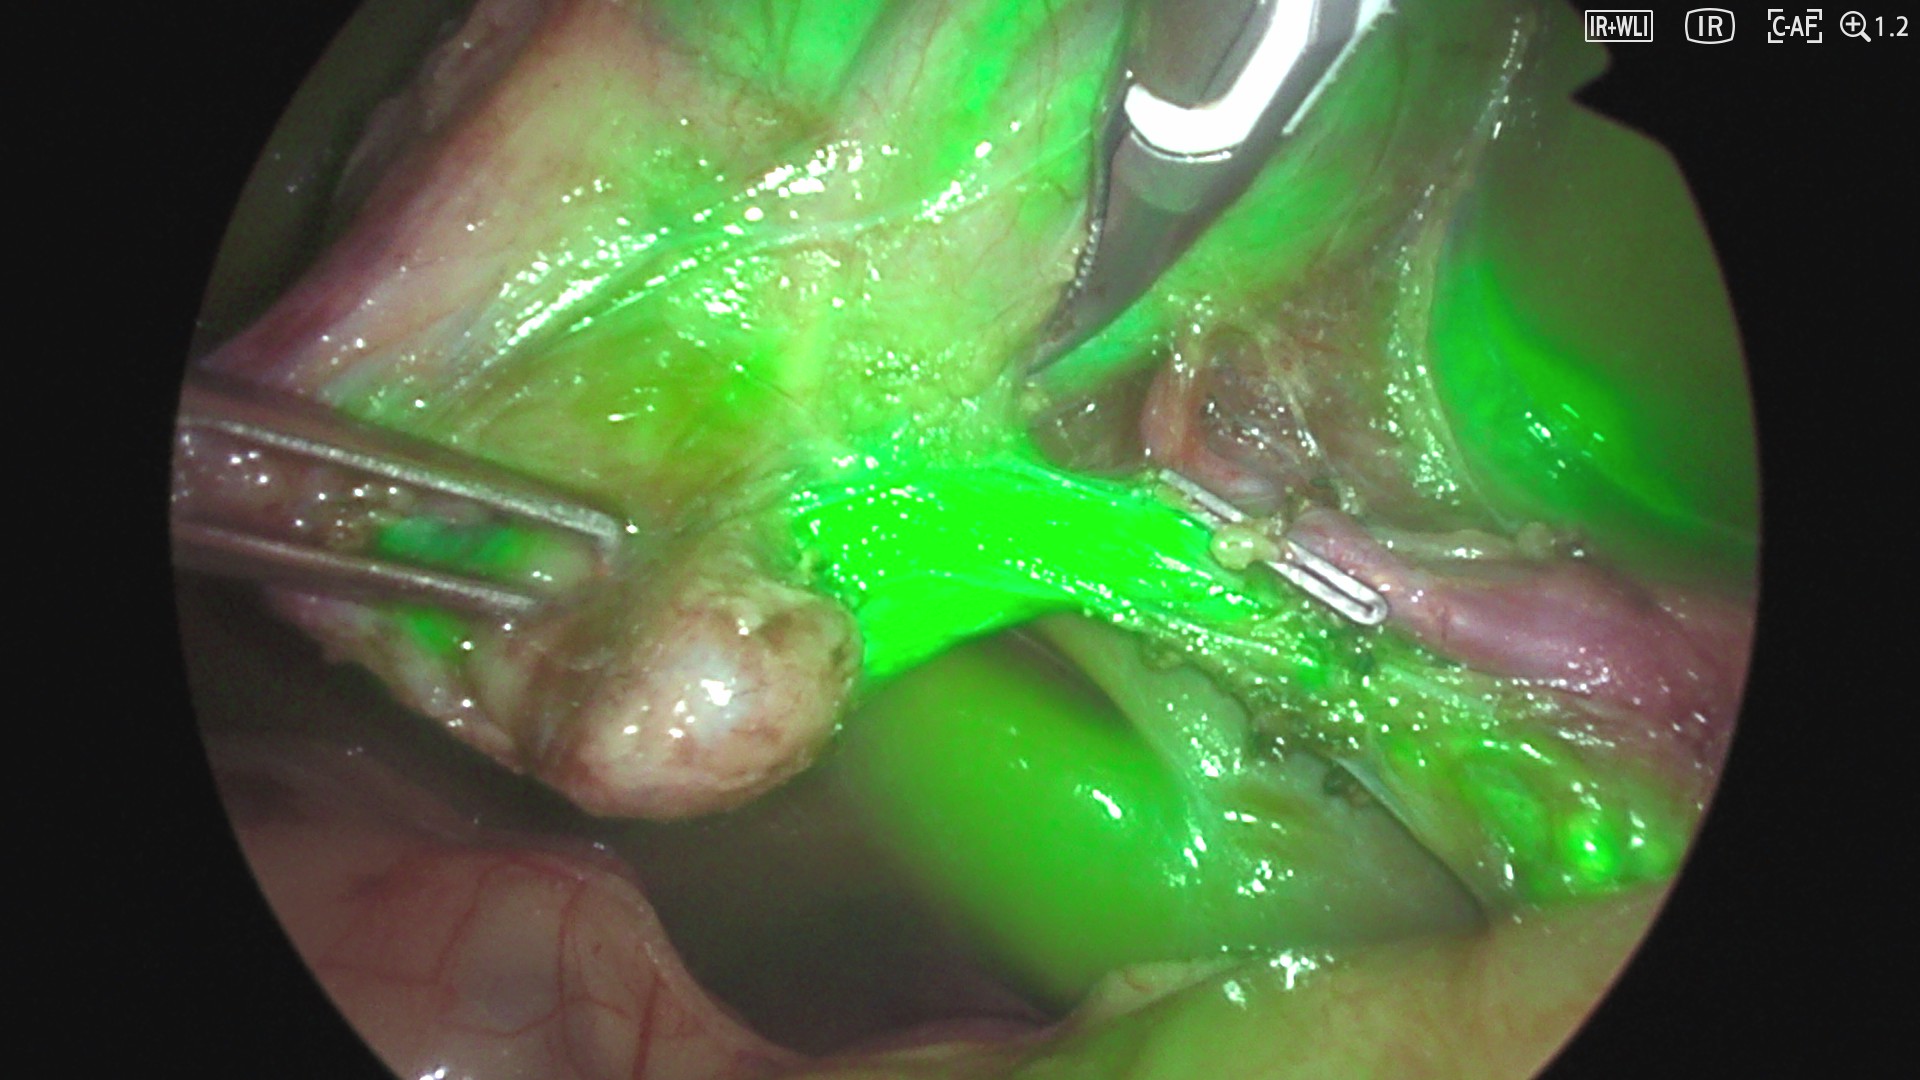

目的:吲哚菁绿(ICG)荧光成像增强小儿腹腔镜胆囊切除术(LC)中胆道的可视化,有助于识别解剖变异和预防胆管损伤。标准儿科建议术前16-24小时给予ICG;然而,这可能不切实际。本研究旨在评价短间隔ICG给药的安全性和有效性。方法:一项前瞻性单中心研究(2024年10月- 2025年6月)纳入了术前静脉注射Verdye®的儿科LC患者。术中使用5分Likert量表、HELPFUL(有用性)和DISTURBED(肝脏背景干扰)评分评估肝外胆道解剖的可视化。数据包括适应症、ICG时机、手术时间和根据Clavien-Dindo分类(C-D)的并发症。结果:纳入11例患者(64%女性),中位年龄14岁(IQR 12,7-15,7),中位体重65,5 kg (IQR 46,5-80)。5例BMI值为25 kg/m2;5例(46%)术前行ERCP。ICG(中位剂量0.34 mg/kg)在手术前225分钟给予。中位手术时间65 min (IQR 58 ~ 68)。中位李克特评分为5分;帮助3;干扰1。无icg相关或C-D并发症发生。结论:短时间间隔ICG用于提高小儿LC时胆道的可视性是安全、可行和有效的。该方法耐受性良好,提供无并发症的高质量成像。

Purpose: Indocyanine green (ICG) fluorescence imaging enhances biliary visualization during pediatric laparoscopic cholecystectomy (LC), helping to identify anatomical variants and prevent bile duct injury. Standard pediatric recommendations suggest ICG administration 16-24 h preoperatively; however, this may be impractical. This study aims to evaluate the safety and effectiveness of short-interval ICG administration.

Methods: A prospective single-center study (October 2024-June 2025) included pediatric LC patients receiving intravenous Verdye® preoperatively. Visualization of extrahepatic biliary anatomy was assessed intraoperatively using a 5-point Likert scale, HELPFUL (usefulness), and DISTURBED (liver background interference) scores. Data included indication, ICG timing, operative time, and complications according to the Clavien-Dindo classification (C-D).

Results: Eleven patients (64% female), median age 14 years (IQR 12,7-15,7) and median weight 65,5 kg (IQR 46,5-80), were included. Five had BMI > 25 kg/m2; five (46%) underwent preoperative ERCP. ICG (median dose 0.34 mg/kg) was administered a median of 225 min before surgery. Median operative time was 65 min (IQR 58-68). Median Likert score was 5; HELPFUL 3; DISTURBED 1. No ICG-related or C-D complications occurred.

Conclusion: Short-interval ICG administration was safe, feasible, and effective in enhancing biliary visualization during pediatric LC. This approach was well-tolerated and provided high-quality imaging without complications.